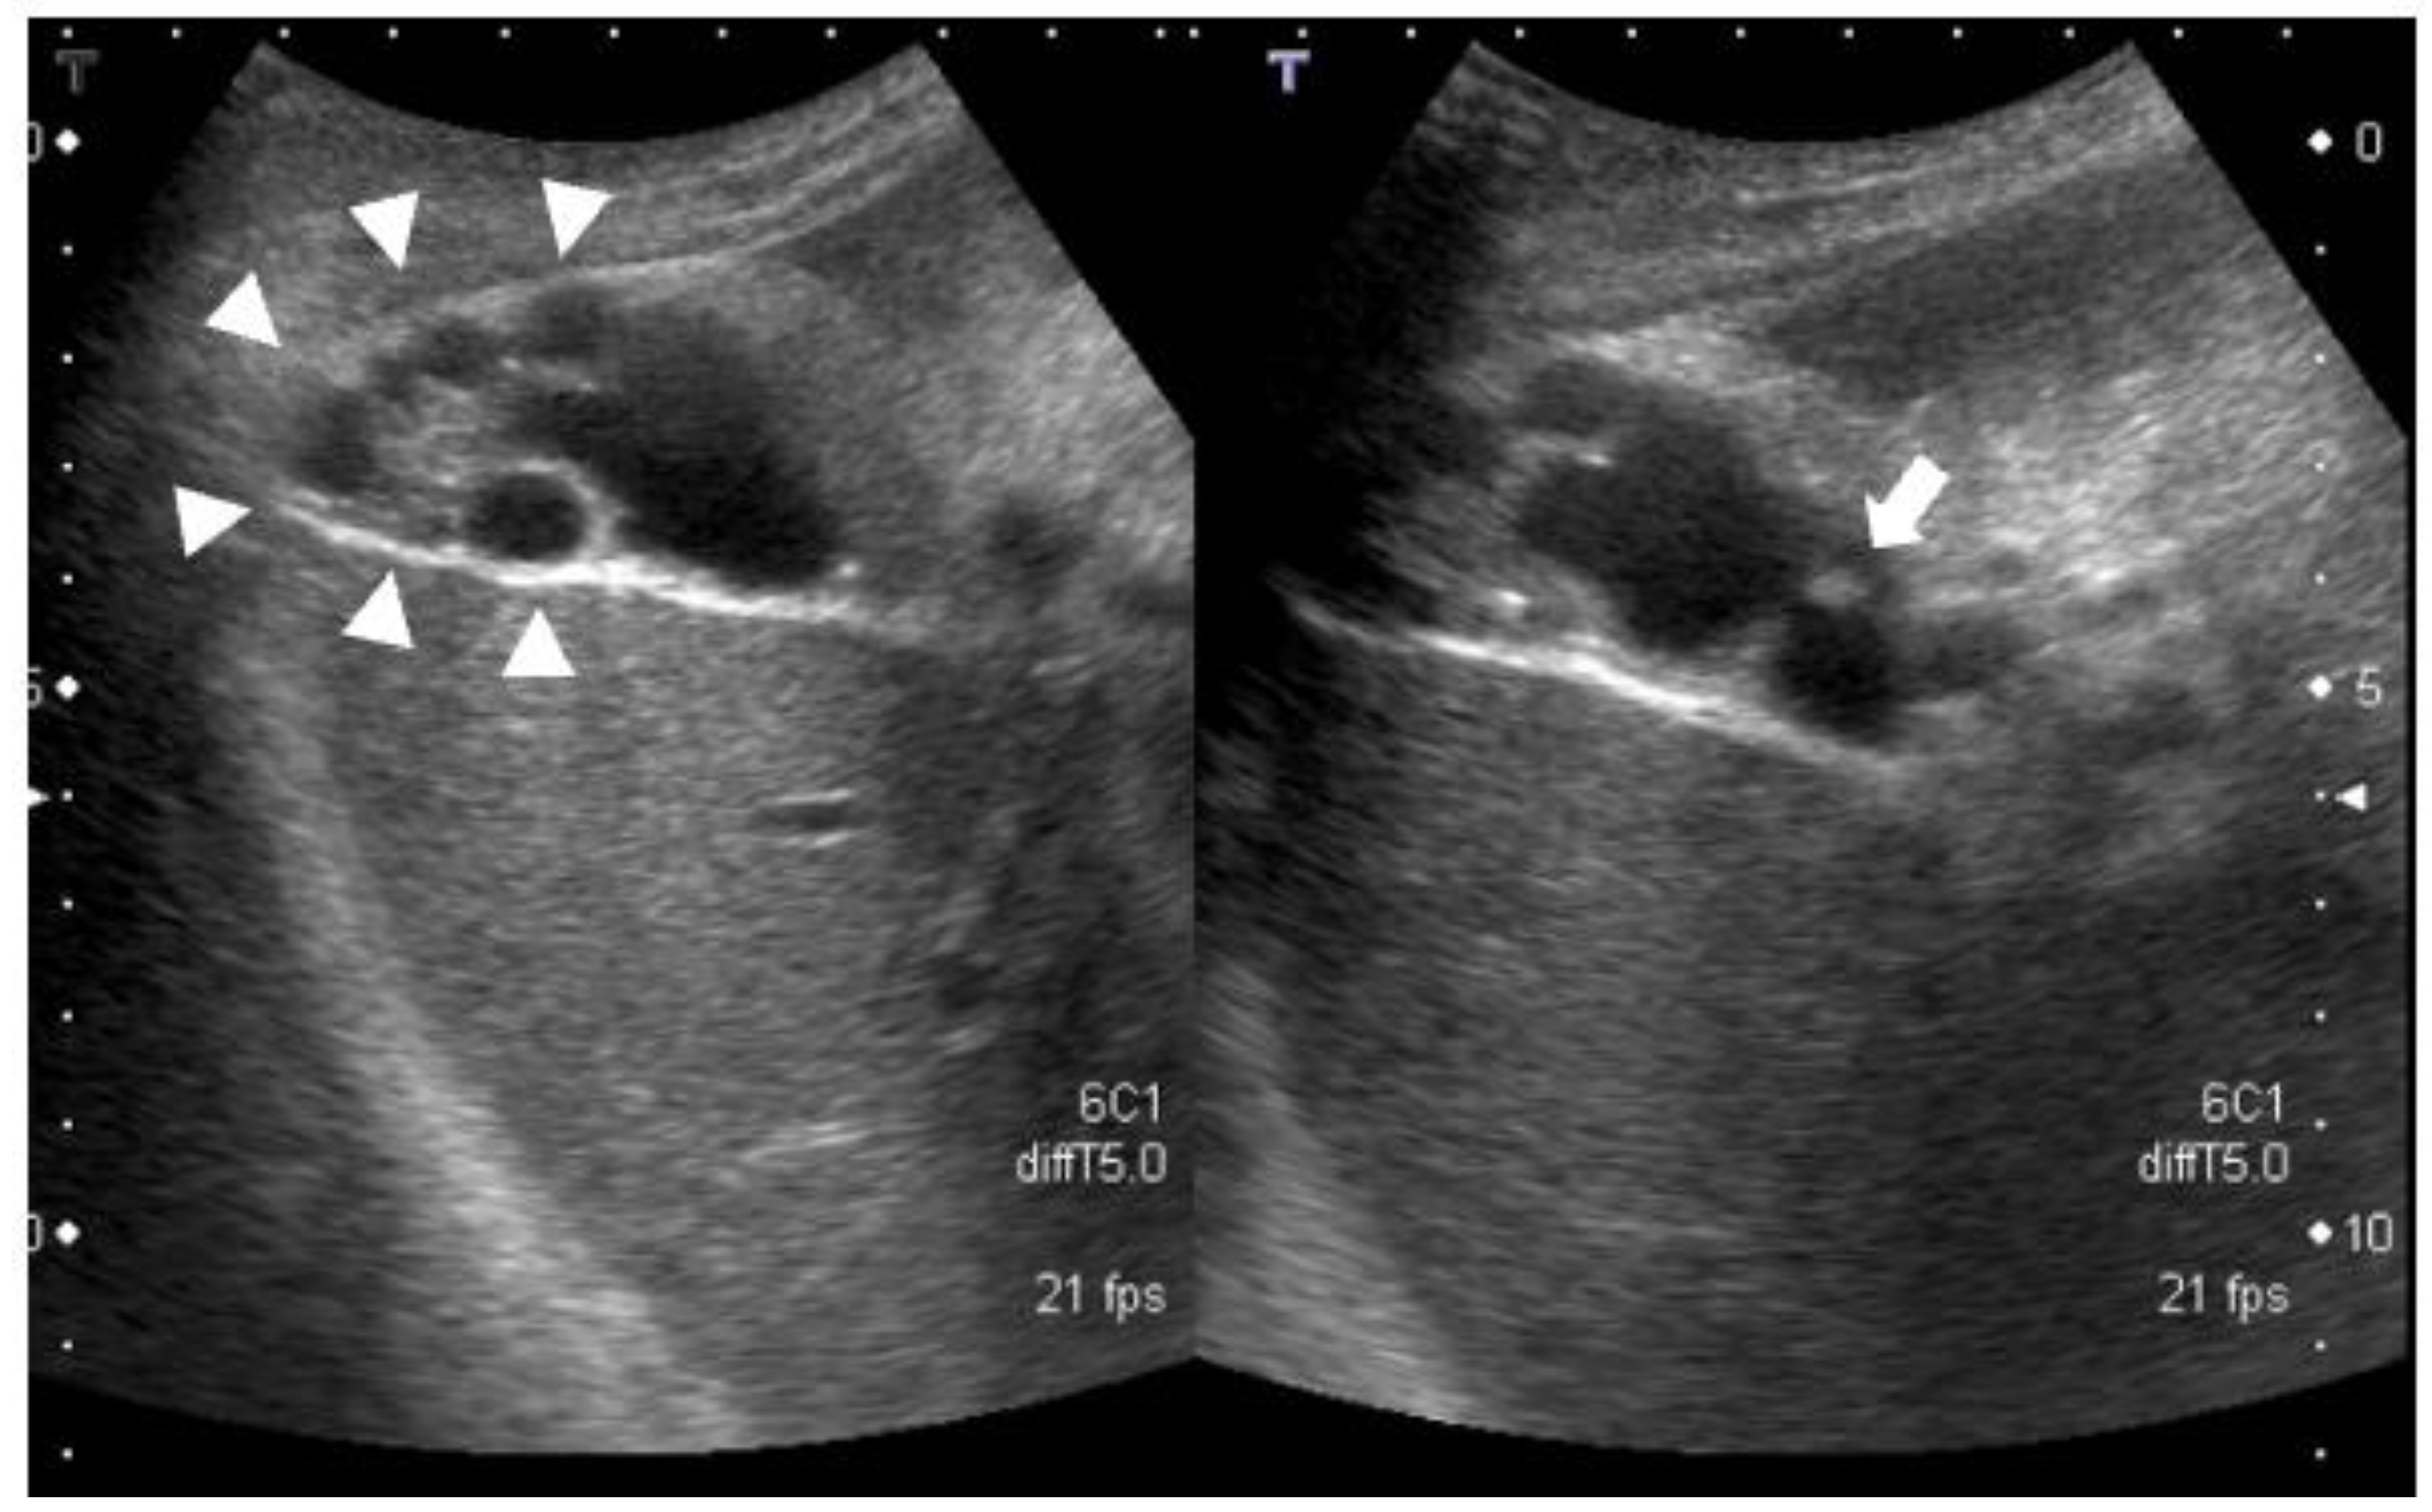

- Abdominal ultrasonography: a 7.4-mm stalked polyp on the gallbladder body and wall thickening of the fundus with aggregated multiple cystic structures was seen, suggesting RAS (Figure 1).